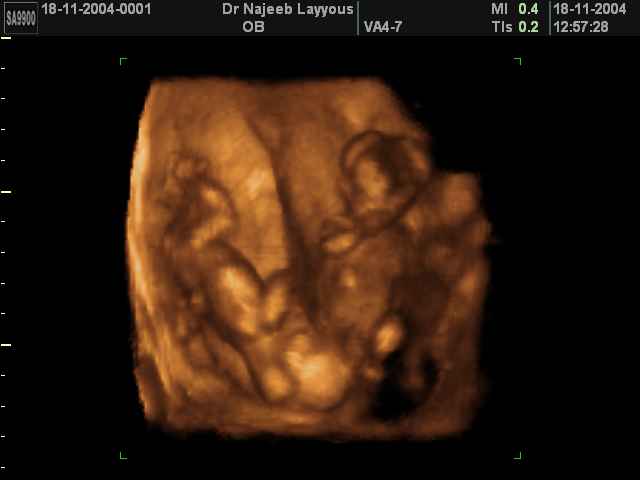

- لقطات فيديو للجنين بجهاز الموجات فوق صوتية رباعي الأبعاد

- صور لوجه الجنين في داخل الرحم

- صور جانبية لرأس الجنين

- صور لأعضاء الجنين

- صور لأطراف الجنين

- صور للجنين في المراحل الأولى من الحمل

- صور لتصرفات الجنين داخل الرحم

- صور لتوائم

- صور للجنين في المراحل المتوسطة من الحمل